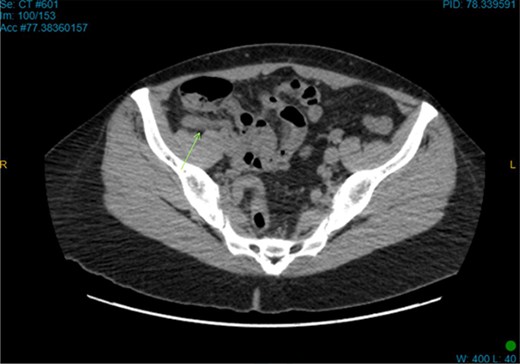

On examination, the patient was alert, but was grimacing in pain. Her abdomen was soft but extremely tender on the right iliac fossa (RIF) region with positive Rovsing’s sign, and rebound tenderness was noted. Vitals were stable. The white cell count was 16.8 × 109/L with left neutrophil shift. The CRP was 102 mg/L. Other laboratory investigations were unremarkable. A computed tomography (CT) scan of the abdomen showed a thickened appendix with adjacent fat stranding which was consistent with acute appendicitis (Figs 1 and 2). Intravenous Augmentin was given pre-operatively and laparoscopic appendectomy was performed on the same day. The patient recovered uneventfully and was discharged the next day. The histological reports revealed appendiceal diverticulitis with transmural mixed inflammation extending out into subserosa and serosa (Fig. 3).

Coronal CT image. Dilated appendix with mild surrounding fat stranding.